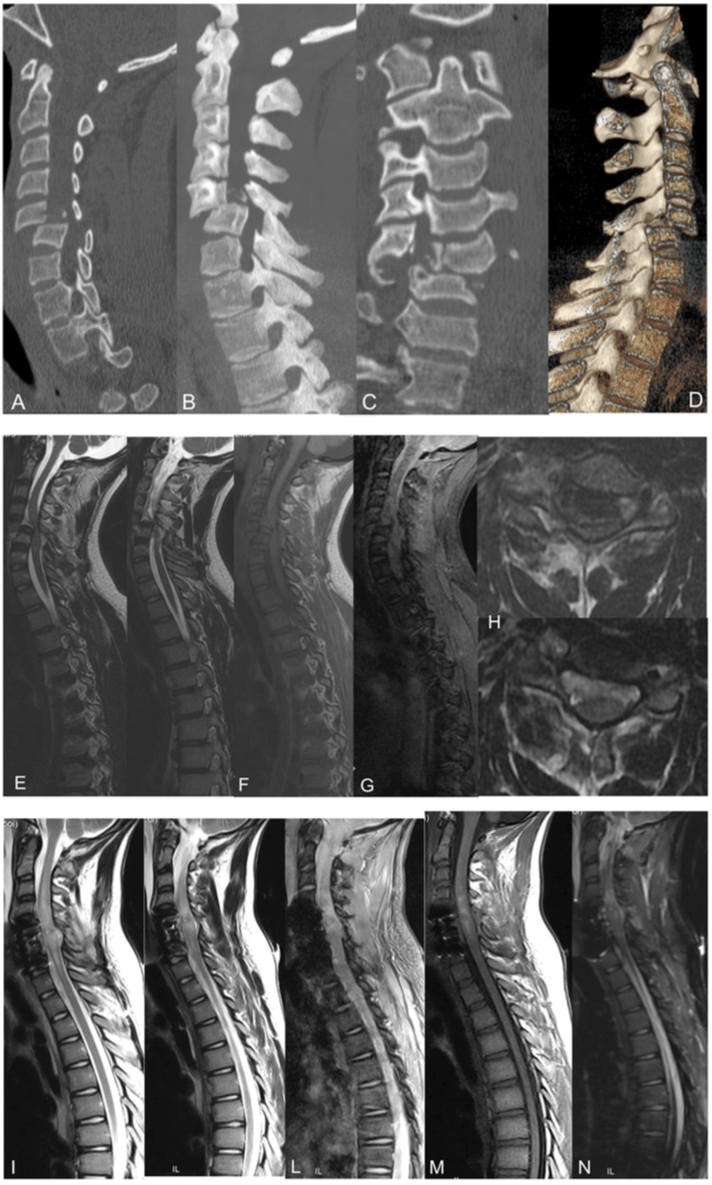

Clasificacion

Las fracturas por compresión en cuña son el resultado de una falla aislada de la columna anterior debido a la flexión hacia adelante. . En las fracturas estables por estallido, las columnas anterior y media fallan debido a una carga de compresión, sin pérdida de integridad de los elementos posteriores. En las fracturas por estallido inestables, las columnas anterior y media fallan en la compresión y la columna posterior se rompe. La columna posterior puede fallar en compresión, flexión lateral o rotación. Existe una tendencia a la cifosis postraumática y los síntomas neurales progresivos debido a la inestabilidad. Si las columnas anterior y media fallan en la compresión, la columna posterior no puede fallar en la distracción.  En las lesiones por distracción por flexión, el eje de flexión es posterior al ligamento longitudinal anterior. La columna anterior falla en compresión, mientras que las columnas media y posterior fallan en tensión. Esta lesión es inestable porque el ligamento amarillo, los ligamentos interespinosos y los ligamentos supraespinosos suelen estar alterados. Las lesiones traslacionales se caracterizan por una mala alineación del canal neural, que ha sido totalmente interrumpido. Por lo general, las tres columnas han fallado por corte. A nivel afectado, una parte del canal espinal se ha desplazado en el plano transversal